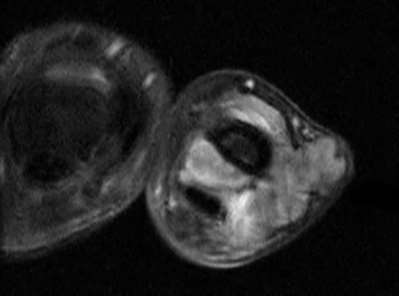

A 35-year-old woman reports wrist pain after a fall onto an outstretched hand. On exam, she has focal tenderness over the wrist snuffbox. A radiograph and CT image are shown in Figures A and B. What is the proper treatment of her injury?